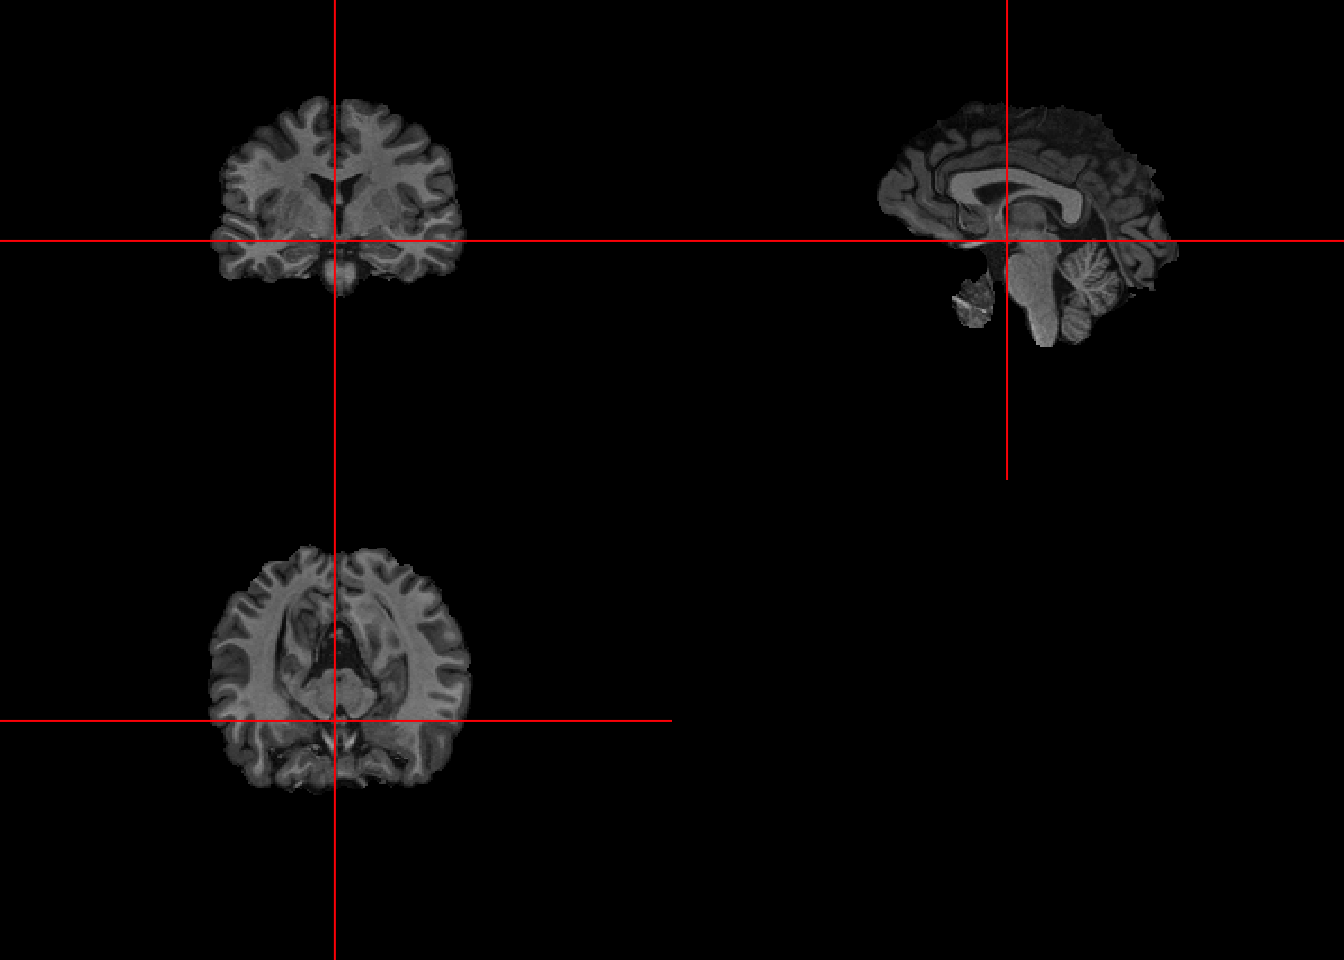

7.5 Visualizing first and second pass

The results have improved, removing much of the lower non-brain sections. However, we can see the results are not perfect so it’s important to visually inspect each image at each phase of the processing pipeline.